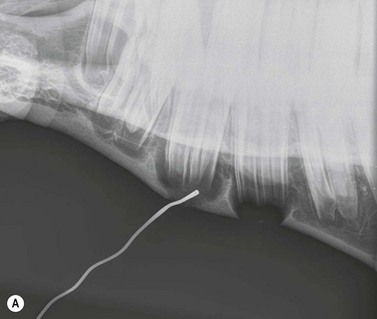

image image

Fig. 13.22 (A & B) A blunt metallic probe placed into a cutaneous discharging tract and secured with radiolucent tape can provide strong evidence as to which tooth is infected in cases of suspected periapical infection.

Fig. 13.23 Lateral oblique radiographs with a blunt metallic probe in place in cases of periapical infection with discharging cutaneous tracts involving the mandibular (A) and rostral maxillary (B) cheek teeth.